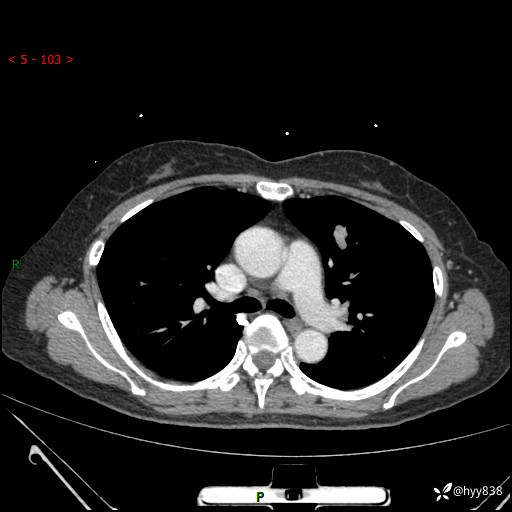

54岁/女,发现肺占位1天。观其形态和强化,术前我信心十足,术后我---结果公布~

【患者信息】:54岁/女

【主诉】:发现肺占位1天

【现病史及既往史】:患者2023.10.23体检发现肺占位:,2023.10.23当地区中心卫生院胸腹部CT:1.左肺上叶结节,考虑为占位可能;2.肝脏小囊肿灶;3.子宫左侧附件区畸胎瘤;无咳嗽咳痰,无恶心呕吐,无发热,无胸闷胸痛等不适;现患者为求进一步诊治来我院,门诊以“肺占位”收入我科。 患者自起病以来,精神饮食睡眠一般,大小便正常,体力体重无明显下降。

【检查】:胸部CT增强(外院平扫)